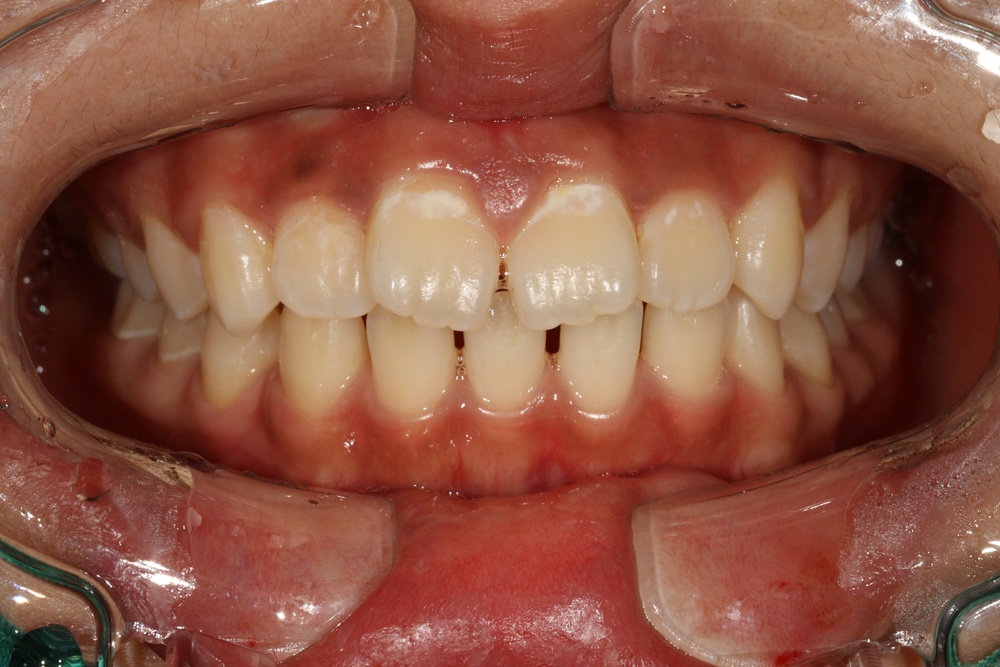

이전에 다쳐서 타치과에서 레진으로 때운 앞니가 시리다고 하셔서 신경치료를 먼저 진행했습니다.

뻗친 앞니를 넣기 위해 위쪽만 작은어금니를 2개 발치하고 공간을 닫았습니다.

교정치료 마무리 단계에서 보철(크라운)을 제작하여 앞니에 끼워드렸습니다.

치료 후 위 앞니가 들어가면서 얼굴모습도 예뻐지고, 앞니로 면을 끊어먹을 수 있게 되었습니다.

앞니 형태와 색상도 이전보다 개선되었습니다.